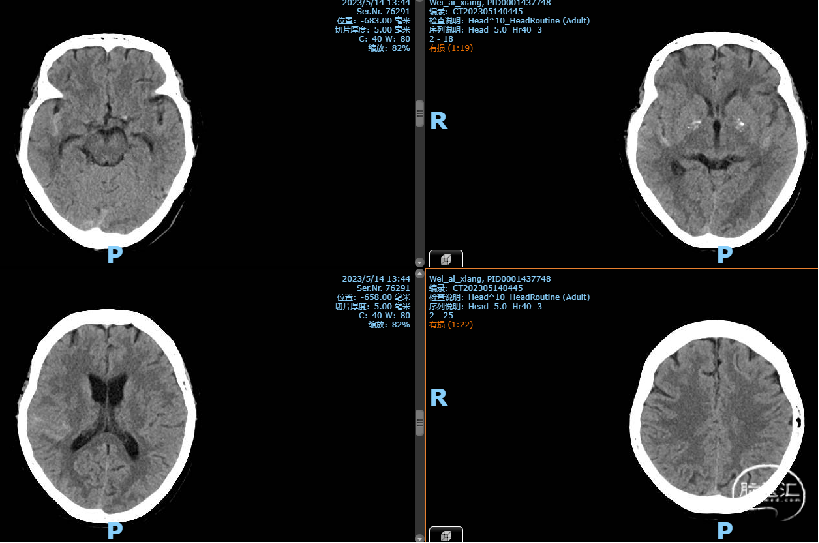

因“头晕3个月” 非急诊入院当地医院头部CT:SAH

2023-05-12 术后CT